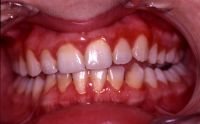

En volymökning av mjukvävnaden kring tänderna som är associerad med intag av läkemedel tillhörande grupperna antiepileptika, immunosuppressiva läkemedel och kalciumblockerare.

Inflammation är den utlösande faktorn som driver tillväxten av mjukvävnaden därför är plackkontroll av största vikt.

Förekomst av gingivala hyperplasier med djupa tandköttsfickor och svåra hygienförhållanden som följd.